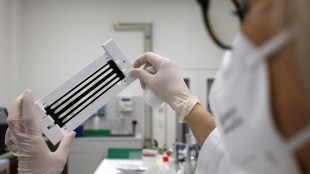

Nuove forbicine molecolari più compatte per modificare il Dna

Efficaci nel correggere l'ipercolesterolemia familiare nei topi